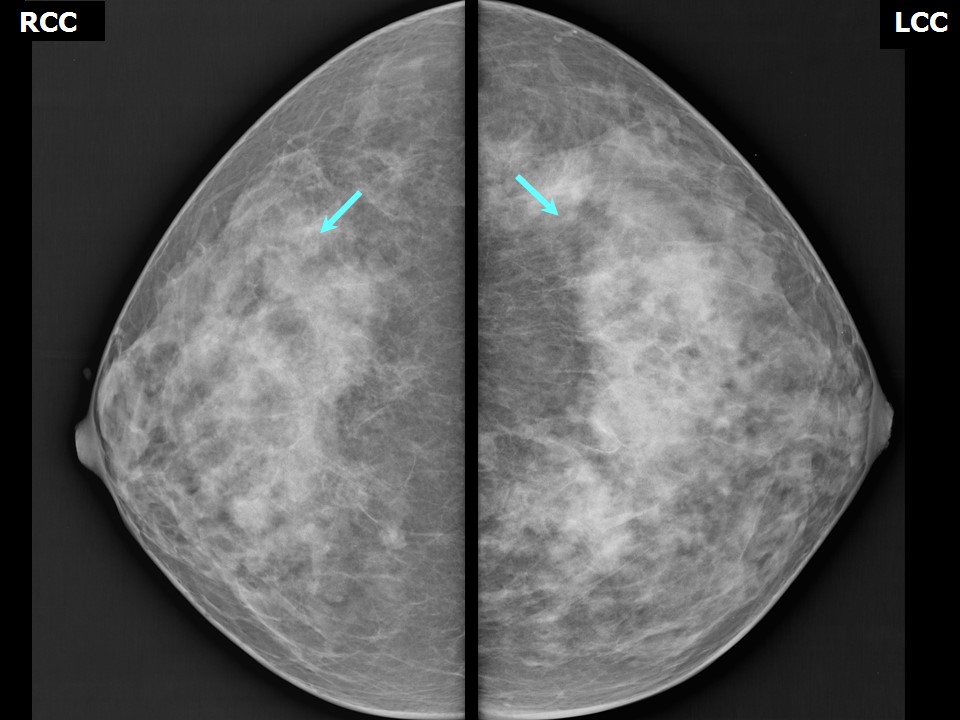

Феномен гипердиагностики в маммографии: примеры и иллюстрации

Раздел: Образы вокруг